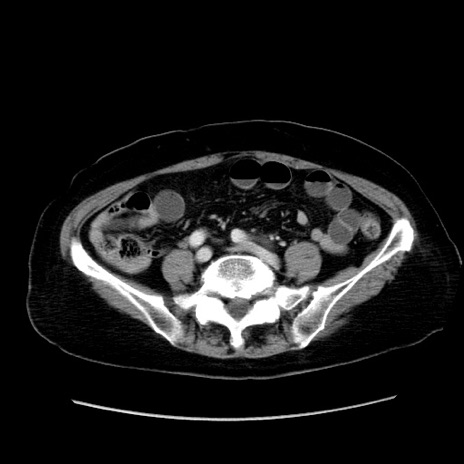

症例19(横断像)

【症例】80歳代女性

【主訴】下腹部痛

【現病歴】約8時間前より下腹部痛の出現あり、救急外来受診。

【既往歴】両側付属器切除

【身体所見】意識清明、下腹部正中に手術痕あり、その部位に一致して圧痛と反跳痛あり。腸蠕動音は亢進。

【データ】WBC 9300、CRP 0.15